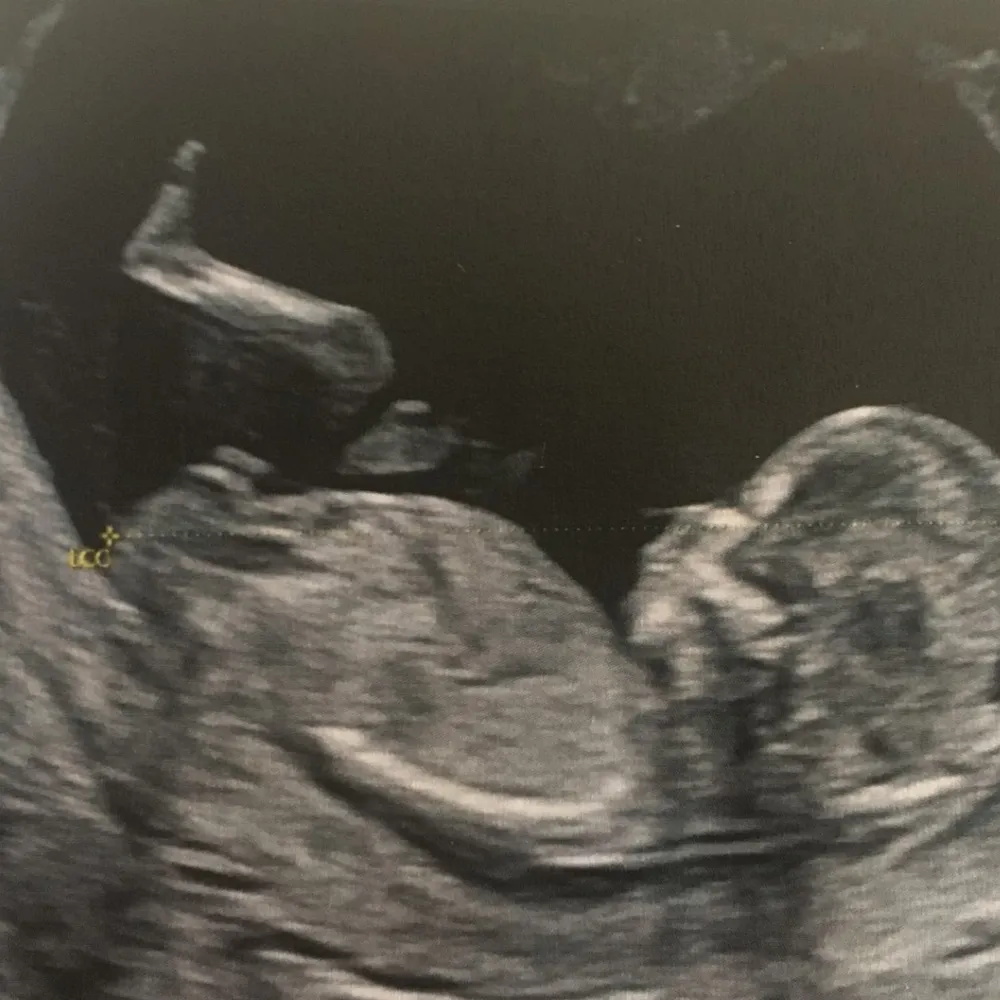

Amélie Ferreira, sage femme échographiste à l'hôpital de Noyal-Pontivy, nous parle de son métier, elle qui voit tout, qui lit tout de la vie in utero. De ce moment en suspens, si particulier qu'est l'échographie dans la vie des futurs parents, et dans celle du bébé à venir. Un examen médical avant tout, qui ne cesse de se transformer au grès des évolutions technologiques, et bientôt avec l'intelligence artificielle.